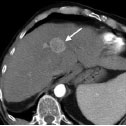

酒精消融术前对比增强CT示肝细胞癌

酒精消融术后对比增强CT示大部分肿瘤无明显增强,提示已阻断血供